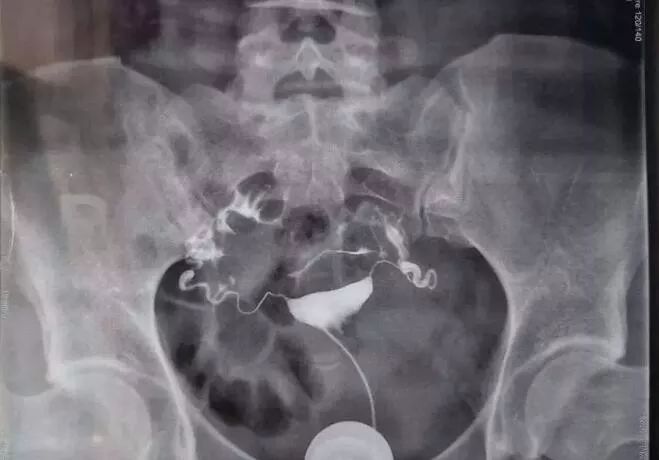

对于不孕症患者,可通过输卵管通液、子宫输卵管造影、宫腹腔镜下输卵管通液术等检查。临床上,首先推荐行子宫输卵管造影。此检查可分类近端或远端堵塞,或通而不畅等,可以为后续治疗方案提供一定参考价值。